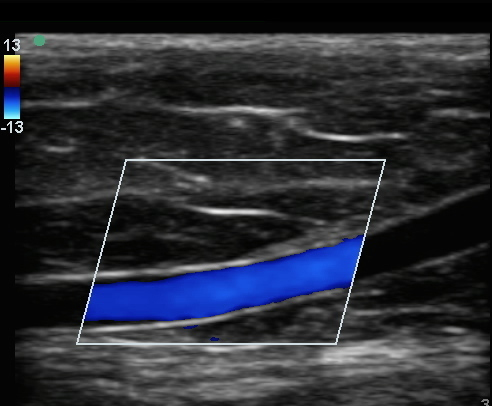

Imagen a color de la vena basílica